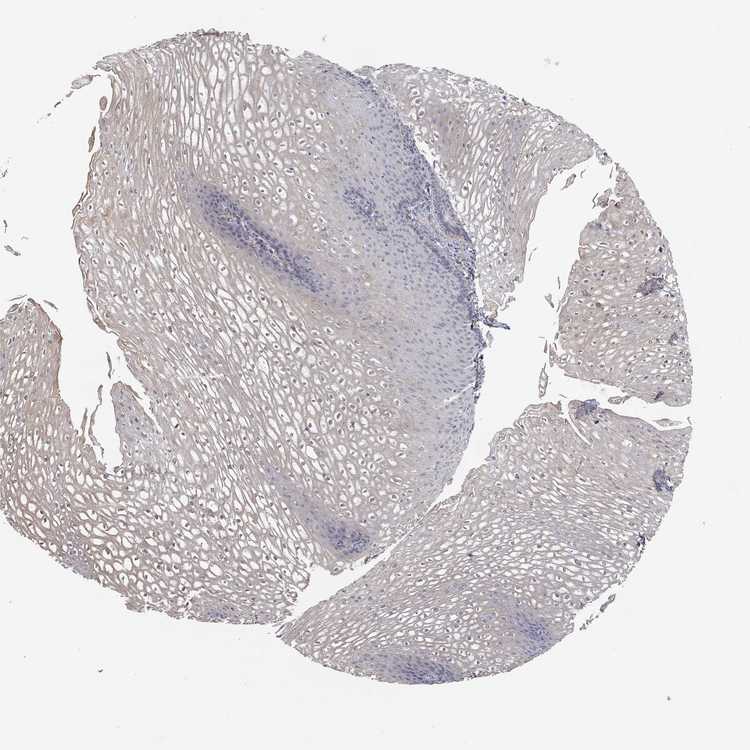

ESOPHAGUS - Antibody stainingi

Antibody staining in the annotated cell types in the current human tissue is reported as not detected, low, medium, or high, based on conventional immunohistochemistry profiling in selected tissues. This score is based on the combination of the staining intensity and fraction of stained cells.

Each image is clickable and will lead to virtual microscopy that enables deeper exploration of all samples and also displays staining intensity scores, fraction scores and subcellular localization as well as patient and tissue information for each sample.

Antibody HPA078654

Squamous epithelial cells Not detected